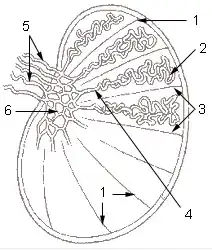

Posição do rete testis dentro do testículo.

| |

1: Septos do testículo

2: Túbulos seminíferos complicados 3: Lóbulos do testículo 4: Túbulos seminíferos retos 5: Dutos eferentes 6: Rete testis | |